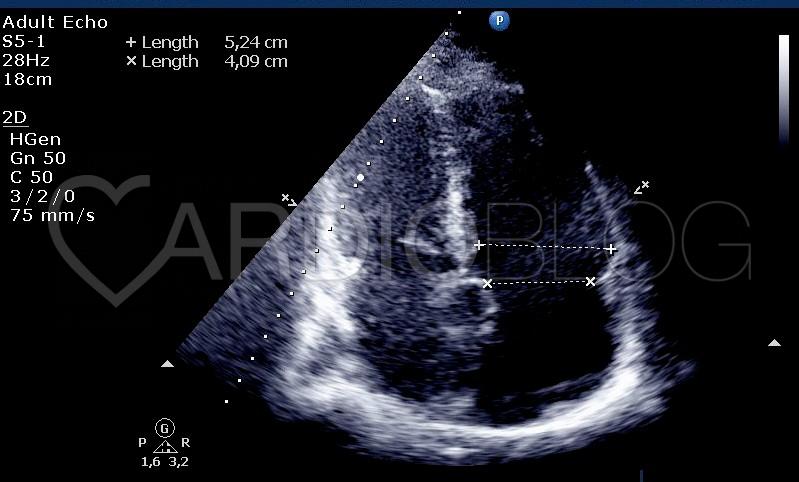

<p>Csúcsi 5-üreg metszetből is jól látható a shunt (video 3.), kinagyítva lemérhető az átmérője is, ami 5 mm (ábra 3.).</p>

<p style="text-align: center;"><a href="http://www.cardioblog.hu/wp-content/uploads/VSD_abra_3_VSD_merete.jpg" target="_blank"><img class="aligncenter size-large wp-image-3109" title="VSD_abra_3_VSD_merete" src="http://www.cardioblog.hu/wp-content/uploads/VSD_abra_3_VSD_merete-704x328.jpg" alt="" width="700" height="326" /></a></p>